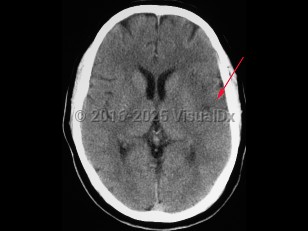

diflucortolone, 50-59 year old Female

231 Diagnoses match 0 of 1 findings